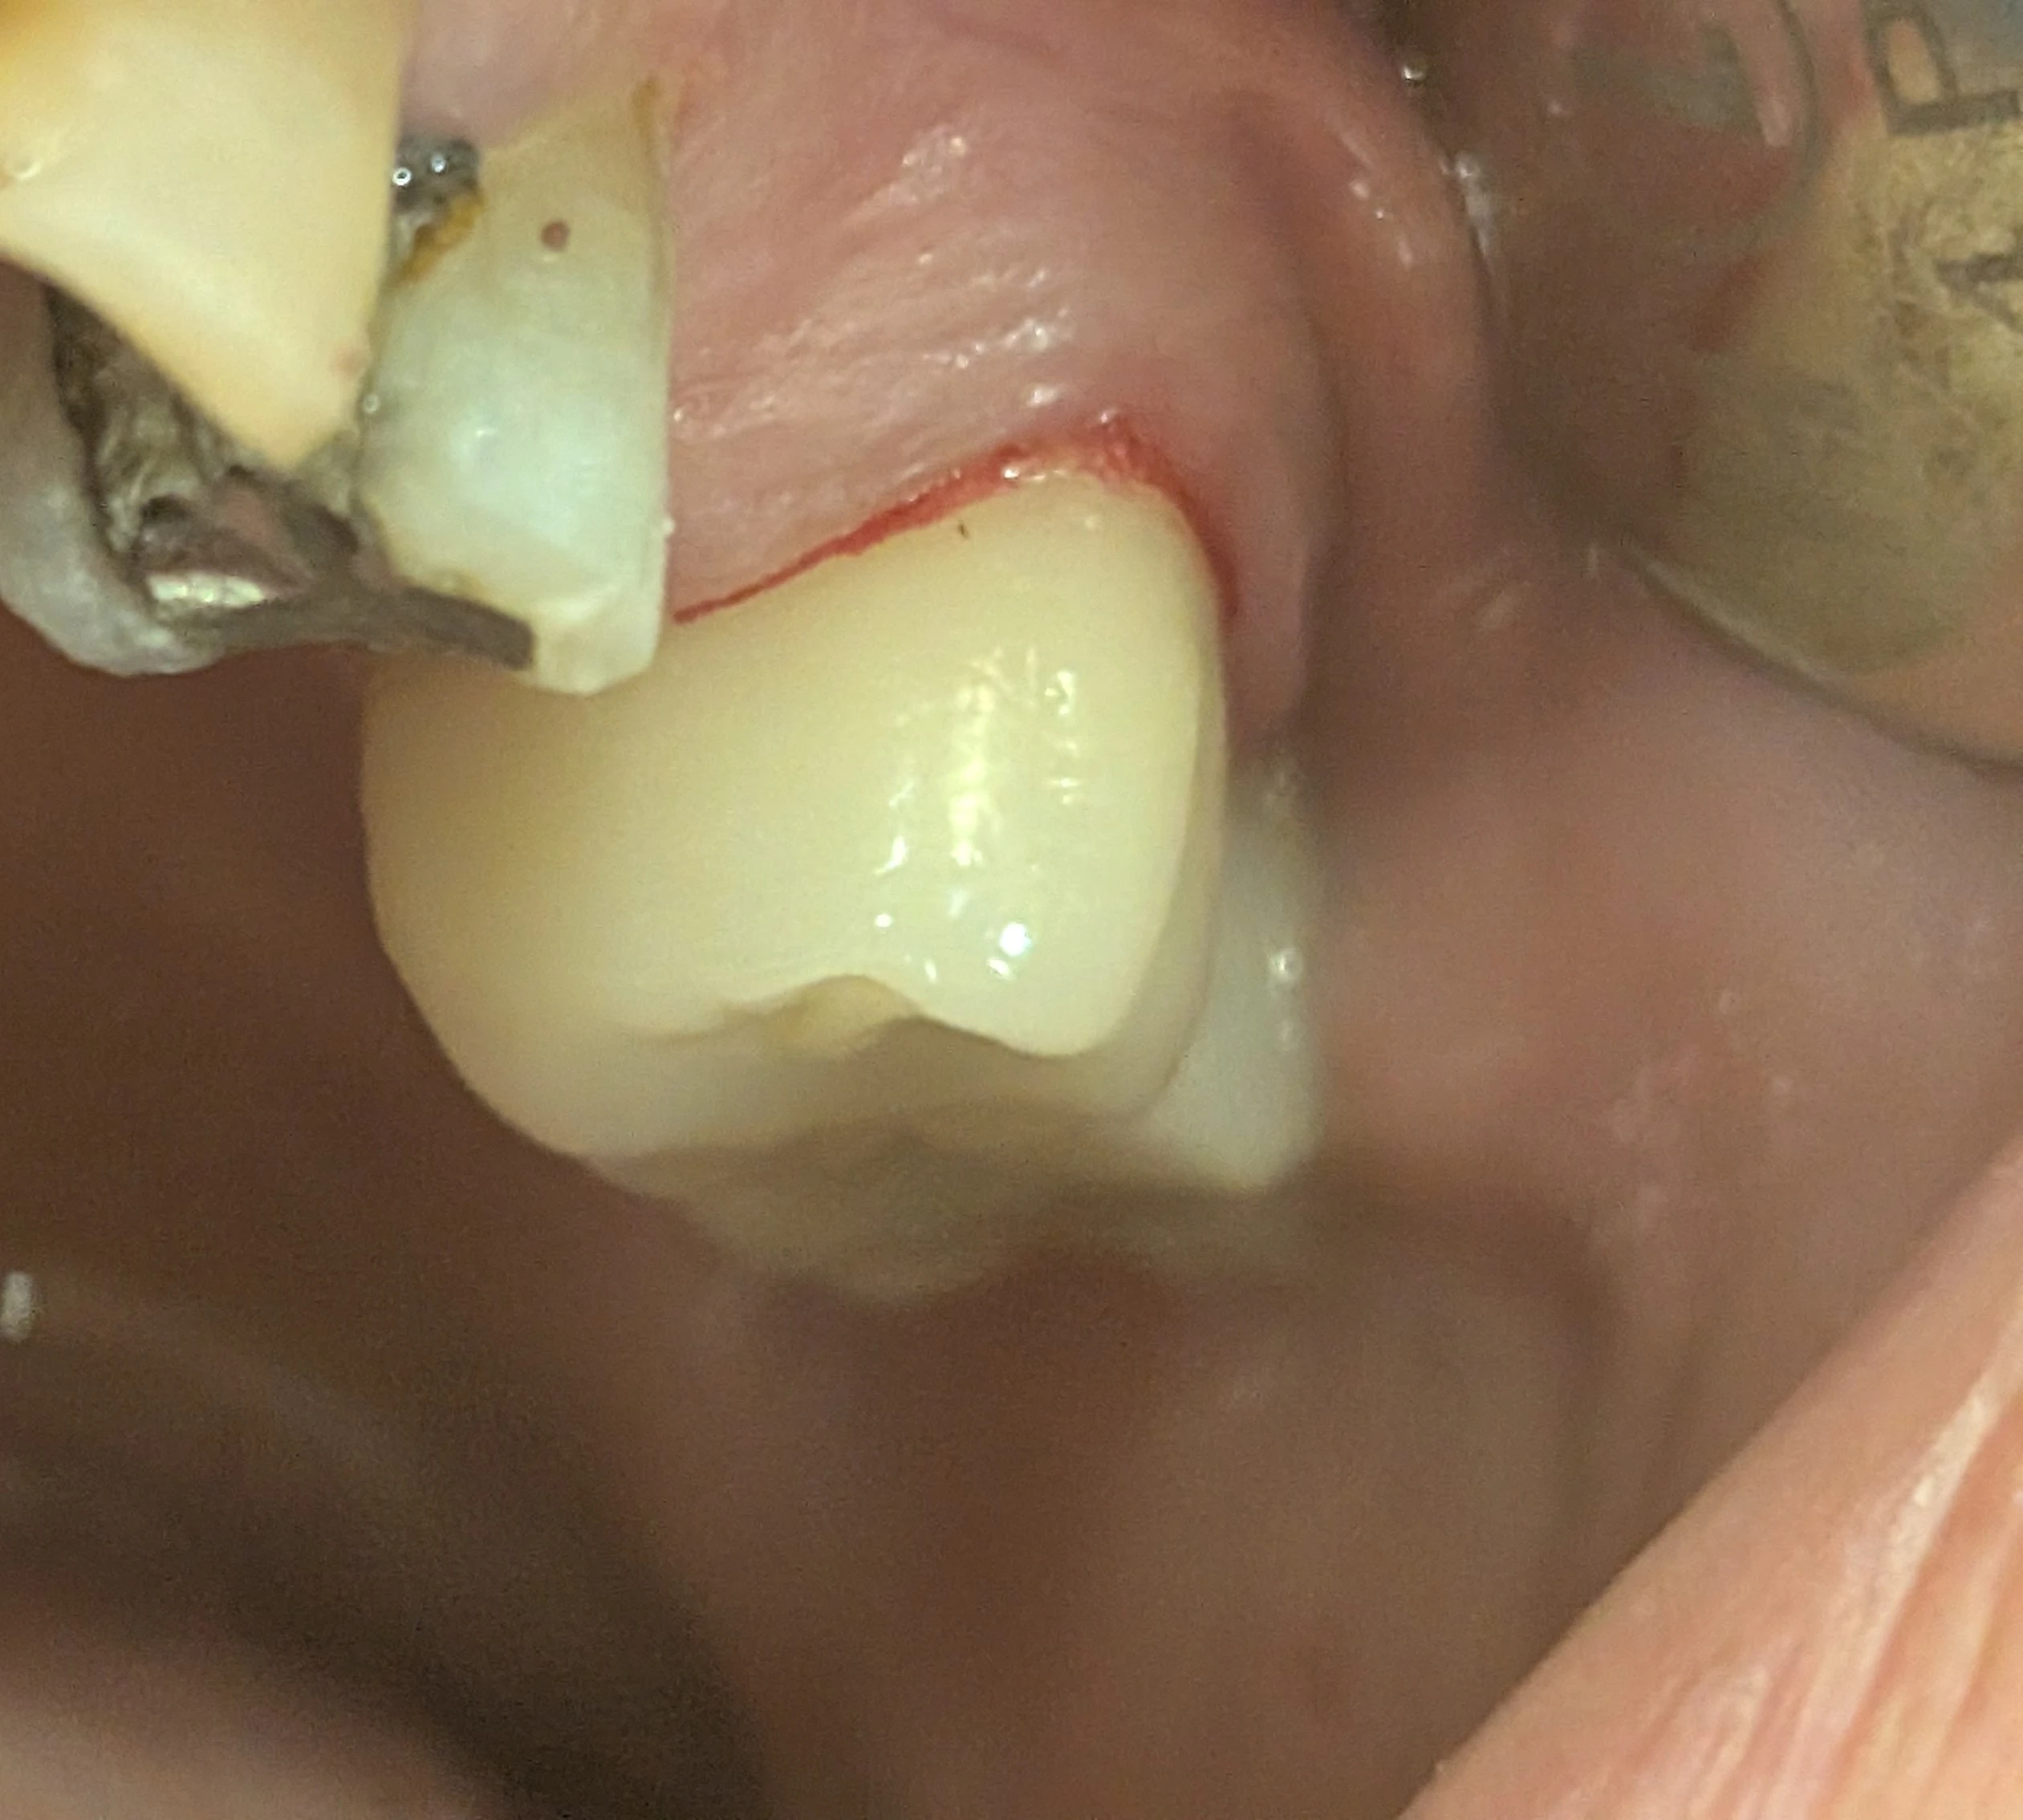

در دندان‌های خلفی، در شرایط طبیعی بیمار عمدتاً سطح باکال دندان را می‌بیند. اما زمانی که دندان مزیالی از دست رفته باشد، سطح مزیال تاج نیز وارد میدان دید می‌شود.

در این وضعیت بیمار ممکن است احساس کند: روکش بزرگ‌تر از حد طبیعی ساخته شده، دندان برجسته یا حجیم است، یا فرم تاج با دندان‌های دیگر هماهنگ نیست؛ در حالی‌که بسیاری از موارد، مشکل ناشی از افزایش سطح قابل رؤیت است، نه افزایش واقعی حجم تاج.